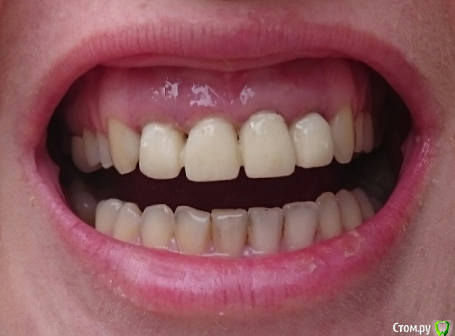

MariaF Опубликовано 10 февраля, 2016 Поделиться Опубликовано 10 февраля, 2016 (изменено) Добрый день, В 2002 году на передние зубы были установлены 4 металло-керамические коронки (cнимок прикрепила).На потемнение десны я не обратила внимания, поэтому когда именно это произошло сказать не могу, но думаю давно. Сейчас собралась их менять и вдруг задалась вопросом о деснах.Важно уточнить, что менять коронки приходится в Турции, и не смотря на мой неплохой турецкий многих терминов я не знаю. Насколько я поняла, под десной во всех 4-х зубах осталась часть родного зуба. Врач сначала удалил инструментом две самые передние коронки ( на их место поставил светлые штифты, материал похож на керамику).Двойки зубы врач предпочел не вытаскивать полностью, а спилить (т.к. побоялся сломать родную часть зуба).В результате остались небольшие части металла. Немного подрезал десну, скорее в косметических целях, т.к. 1 зуб был вроде как короче (фото прикрепила).Теперь ждем заживления.Врачом был выявлен переодонтит, неужели лечение состоит только в "самоизлечении", т.к. ничего назначено не было. Поставил временные коронки (фото прикрепила, как раз на нем хорошо виден большой потемневший участок десен) Новые коронки будут E-max. Хотела бы узнать, от чего могло произойти потемнение, причем такое обширное: из-за 'мертвых' зубов или из-за металла?Если из-за метала, то не будет ли логичнее его удалить? Спасибо за советы! Изменено 10 февраля, 2016 пользователем MariaF 1 1 Ссылка на комментарий

MariaF Опубликовано 17 февраля, 2016 Автор Поделиться Опубликовано 17 февраля, 2016 Уважаемые доктора, Попросила администратора вновь открыть тему.Может у вас будут какие-то предположения на эту тему. Новые коронки все еще не были установлены. Насколько я поняла в состав старых входило серебро, которое и могло дать потемнение. Но потемнение произошло не только у самого зуба, но и выше, что видно на фото. Ссылка на комментарий